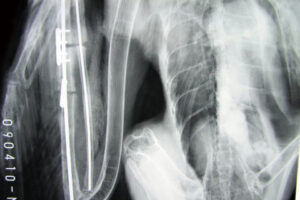

3時間に及ぶ手術によって、バラバラになった翼の骨(6つに割れていました)をつなぎ合わせる手術を行いました。体外に飛び出していた骨や傷口付近の筋肉や腱はすでに乾燥や腐敗が進んでおり、部分的に切除しなくてはなりませんでしたが、残された断端同士をつなぎ合わせ、外見上は正常に近い状態にまで整復しました。

骨が付くまでは安静にして!